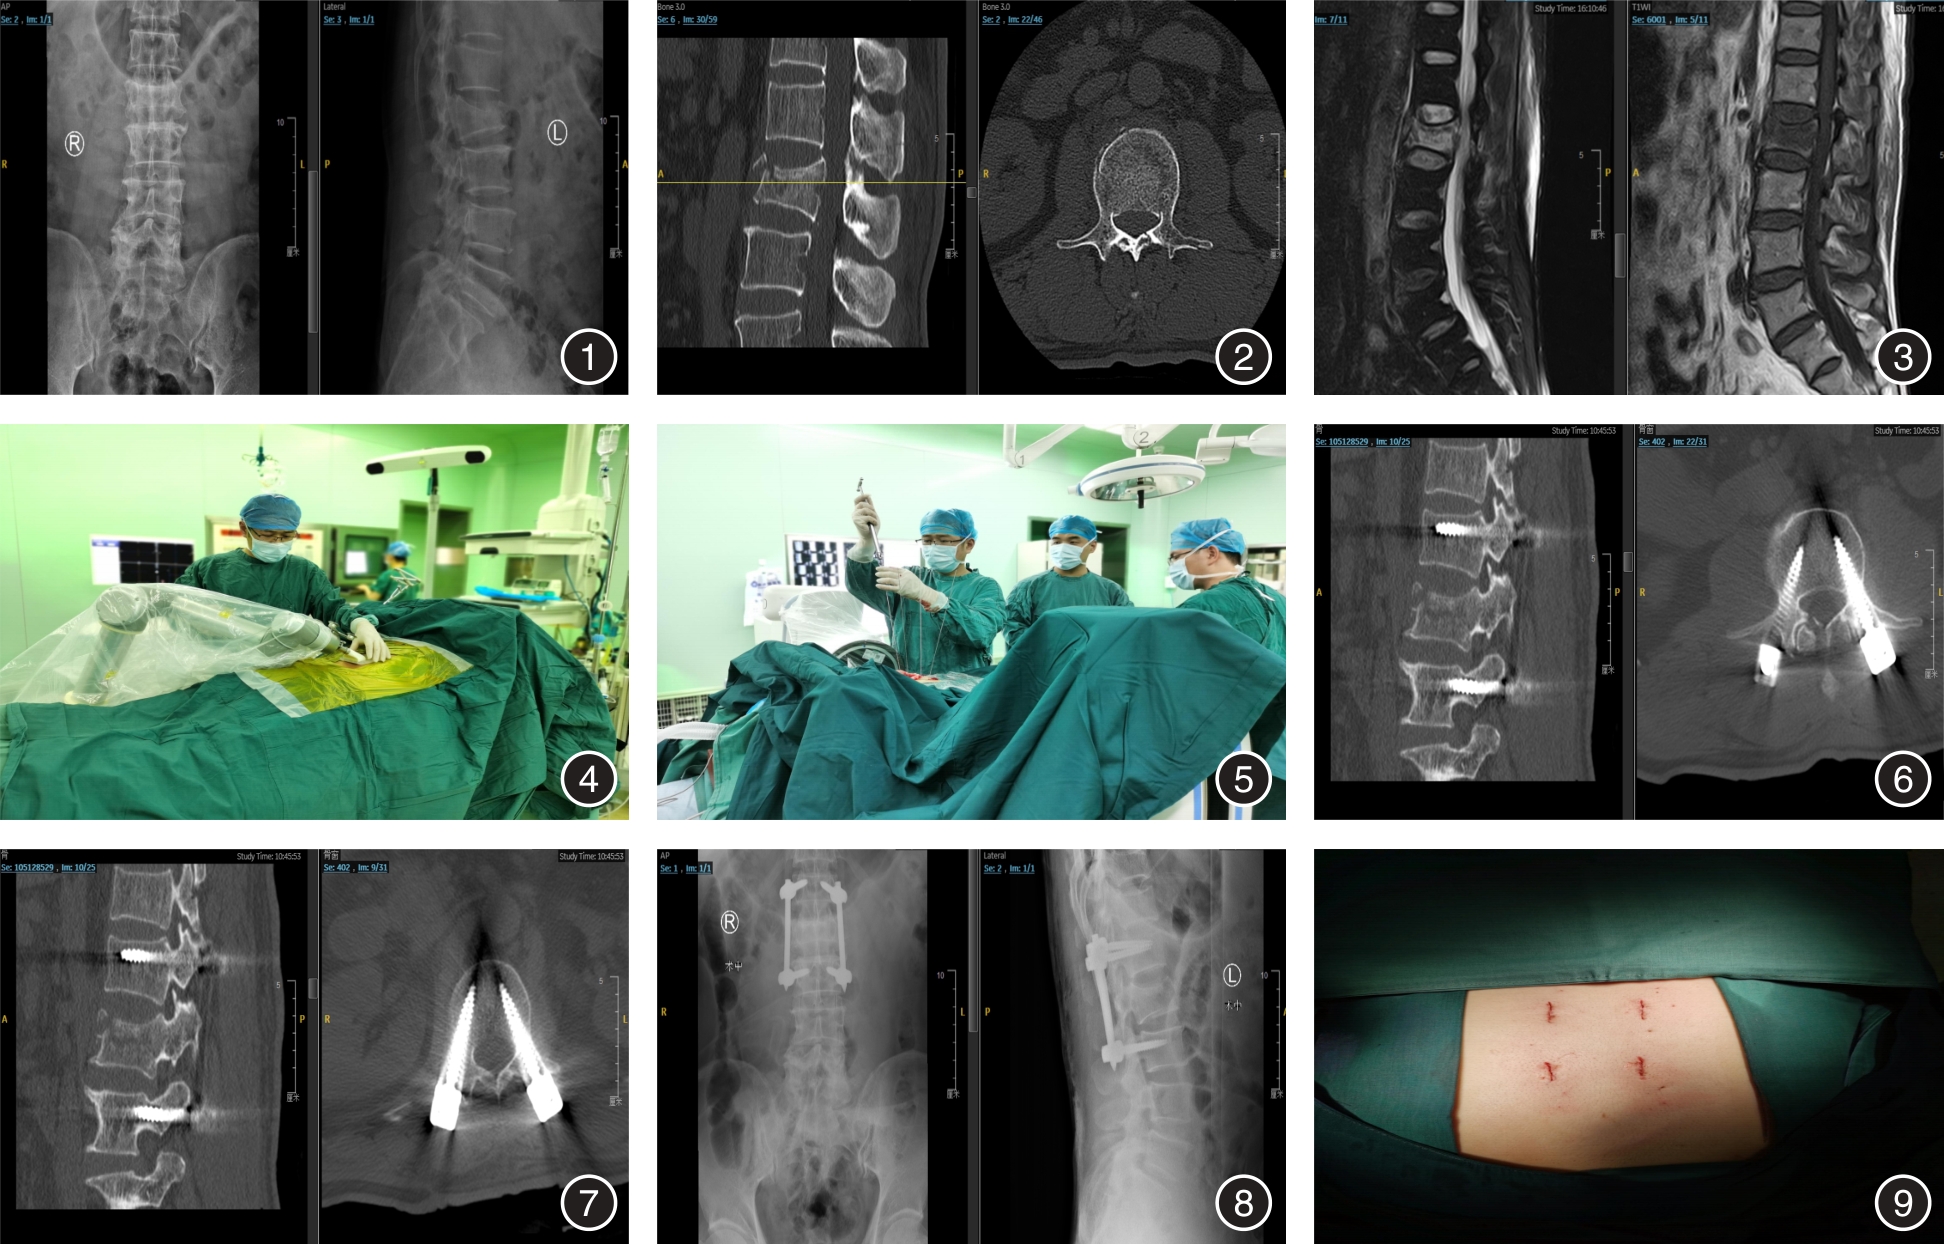

Effect and prognosis of robot assisted percutaneous pedicle screw for thoracolumbar fracture

Objective To explore the efficacy and prognosis of robot-assisted percutaneous pedicle screw (PPS) in the treatment of thoracic and lumbar spine fracture. Methods A total of 84 patients with thoracolumbar fracture were selected from Xuzhou Renci Hospital from November 2018 to November 2022, and divided into study group (42 cases with robot-assisted PPS) and control group (42 cases with free-hand PPS) according to random number rank method. Perioperative indexes, nail placement accuracy, prognostic indexes (VAS score, Cobb Angle, relative height of anterior vertebra) and incidence of postoperative complications were compared between the two groups. Results Less intraoperative blood loss, shorter fluoroscopy time, fluoroscopy times, operative time, single nail placement time and radiation exposure time, and higher nail placement accuracy were observed in the study group (P < 0.05). VAS score and Cobb Angle of the injured vertebrae were lower in the postoperative 3 d and the last follow-up, and the relative height of the injured vertebrae was higher than that before surgery in the two groups (P < 0.05). Conclusion Robot-assisted PPS in the treatment of thoracolumbar fracture has a good application effect, which can shorten the operation time, reduce the intraoperative fluoroscopy times, improve the accuracy of nail placement, and have good safety.